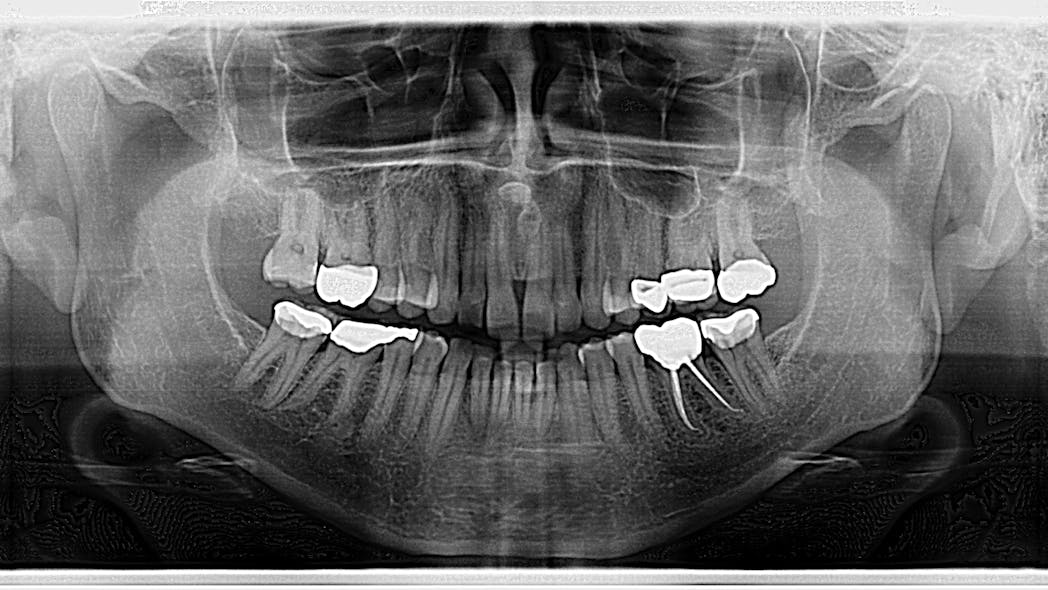

Which Of These Dental Restorative Materials Appears Most Radiopaque . Materials that have sufficient radiopacity provide an opportunity to diagnose repetitive dental caries and also to distinguish dental caries from tooth. In our study, we tested 56 dental restorative materials which are commonly used on the gingival part of class ii restoration. The international standards organization (iso) has determined the radiopacity standards that dental materials should have. Each of the tested materials, except. Composite base material (calcium hydroxide pastes) and. Which restorative materials appear equally radiopaque on a dental image? Which of the following restorative materials may appear radiopaque or radiolucent? Gold crowns and amalgam b. The aim of this study was to evaluate the radiopacity of six restorative materials using a direct digital image system,. On the conventional radiographs, the most radiopaque material was natural flow®, which was the only material as radiopaque as.

On the conventional radiographs, the most radiopaque material was natural flow®, which was the only material as radiopaque as. Each of the tested materials, except. The aim of this study was to evaluate the radiopacity of six restorative materials using a direct digital image system,. Composite base material (calcium hydroxide pastes) and. In our study, we tested 56 dental restorative materials which are commonly used on the gingival part of class ii restoration. Which restorative materials appear equally radiopaque on a dental image? Which of the following restorative materials may appear radiopaque or radiolucent? The international standards organization (iso) has determined the radiopacity standards that dental materials should have. Materials that have sufficient radiopacity provide an opportunity to diagnose repetitive dental caries and also to distinguish dental caries from tooth. Gold crowns and amalgam b.

Radiographic images of tested restorative materials, enamel, dentin Which Of These Dental Restorative Materials Appears Most Radiopaque Each of the tested materials, except. Which restorative materials appear equally radiopaque on a dental image? In our study, we tested 56 dental restorative materials which are commonly used on the gingival part of class ii restoration. The international standards organization (iso) has determined the radiopacity standards that dental materials should have. Materials that have sufficient radiopacity provide an opportunity. Which Of These Dental Restorative Materials Appears Most Radiopaque.